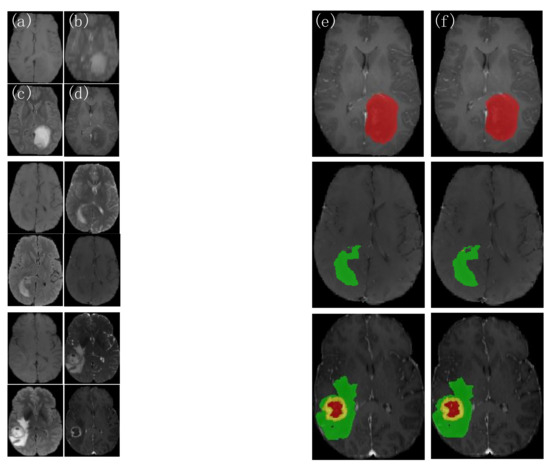

4.3.1. Analysis of the Visualization Results

- The 3D BCS hybrid domain attention mechanism module helps to improve the model’s recognition of the important feature information, and the residual connectivity enhances the segmentation ability. The hybrid loss function can further improve the segmentation accuracy of small targets and optimize the network performance.

- Our model has a low average deviation and a low dispersion, which allows for the further segmentation of the detailed contour of the model.

- In terms of the edge determination and accuracy of the ET and TC tumor areas, the model is superior to other SOTA models, which can help doctors accurately determine the precise location of the incision in surgery and protect patients’ healthy tissues from being removed.